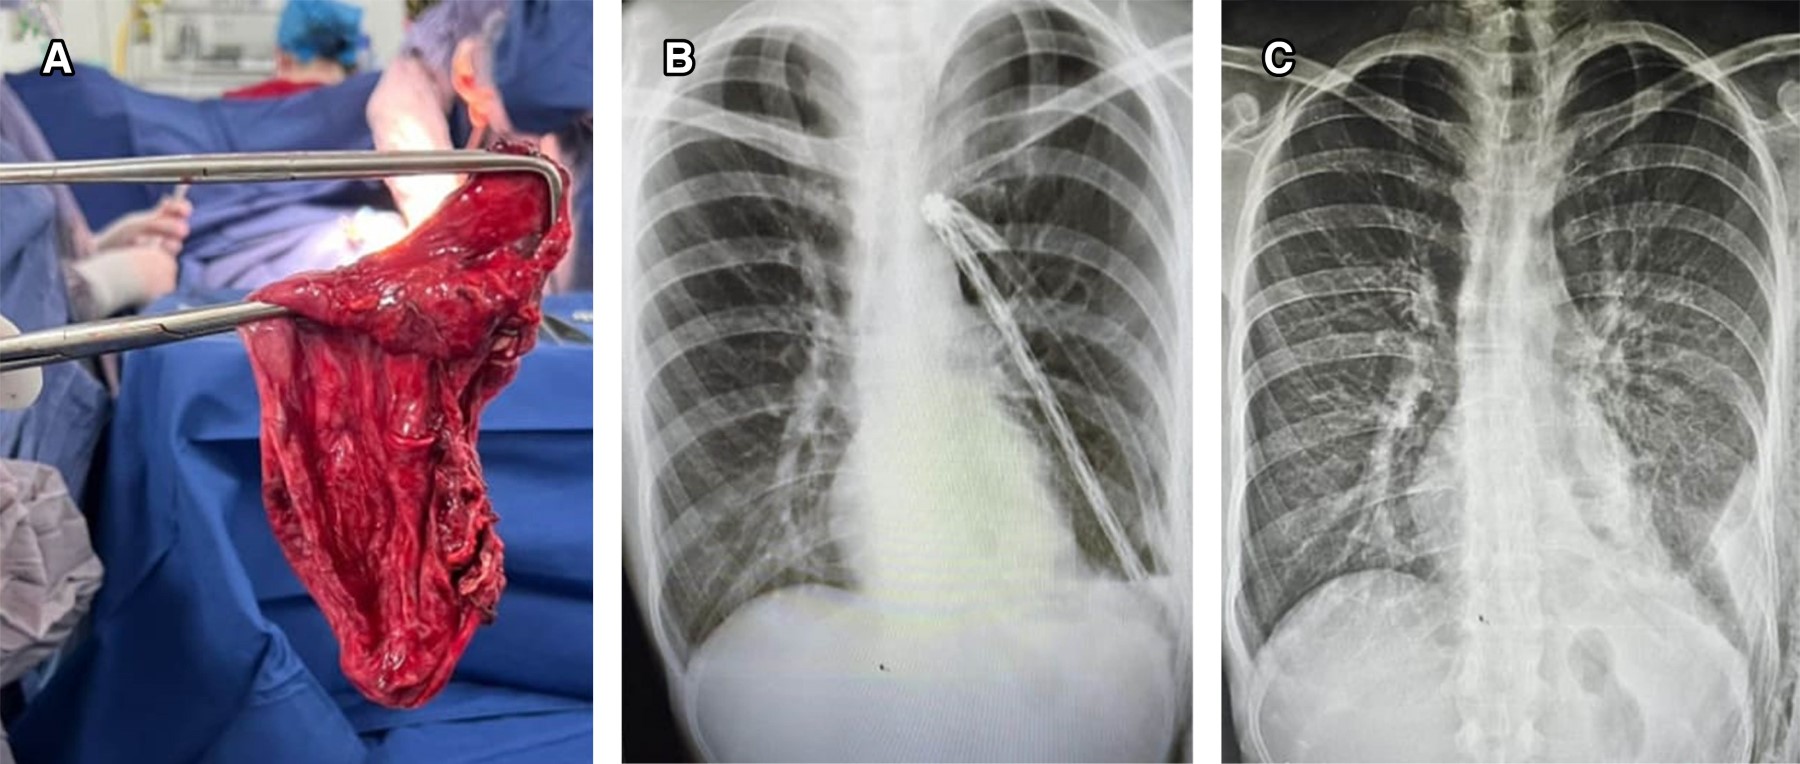

Las causas más comunes de enfisema bulloso incluyen el tabaquismo, la exposición a biomasa y la deficiencia de α-1 antitripsina. Los síntomas incluyen disnea progresiva, tos productiva, disminución de la tolerancia al ejercicio y sibilancias. Las opciones de tratamiento quirúrgico incluyen toracotomía o videotoracoscopia. Al elegir el abordaje ideal para cada paciente, se deben considerar la extensión y la ubicación de las bullas, las comorbilidades y el riesgo de recurrencia, entre otros factores. Presentamos dos casos quirúrgicos: una mujer de 45 años con antecedentes de exposición a biomasa y una bulla gigante que le causó dificultad respiratoria aguda, tratada con éxito mediante toracotomía; y un hombre de 25 años que desarrolló un neumotórax espontáneo con quistes subpleurales asociados con gran altitud, tratado mediante bullectomía videotoracoscópica.

Figura 3